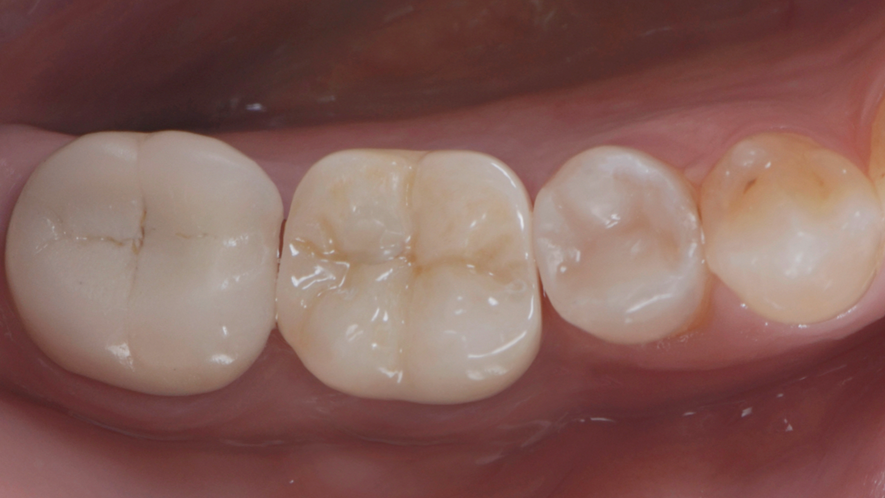

Uma coroa definitiva em zircônia pura foi escolhida neste caso. Desenhada no DentalCad (Exocad), depois de fresada foi maquiada e ajustada num modelo impresso, onde o perfil da mucosa também é impresso em uma resina rosa soft (Figura 11). O análogo digital do pilar Ideale 4,5×4 é inserido no modelo impresso, dando a possibilidade da coroa fresada em Zircônia ser ajustada com mais segurança e precisão.

A instalação da coroa é feita utilizando um parafuso da coifa do pilar Ideale (Figura 12) e nenhum ajuste oclusal e/ou interproximal foi necessário, mostrando a excelente acurácia e adaptação da coroa realizada em fluxo restaurativo 100% digital com o iTero.